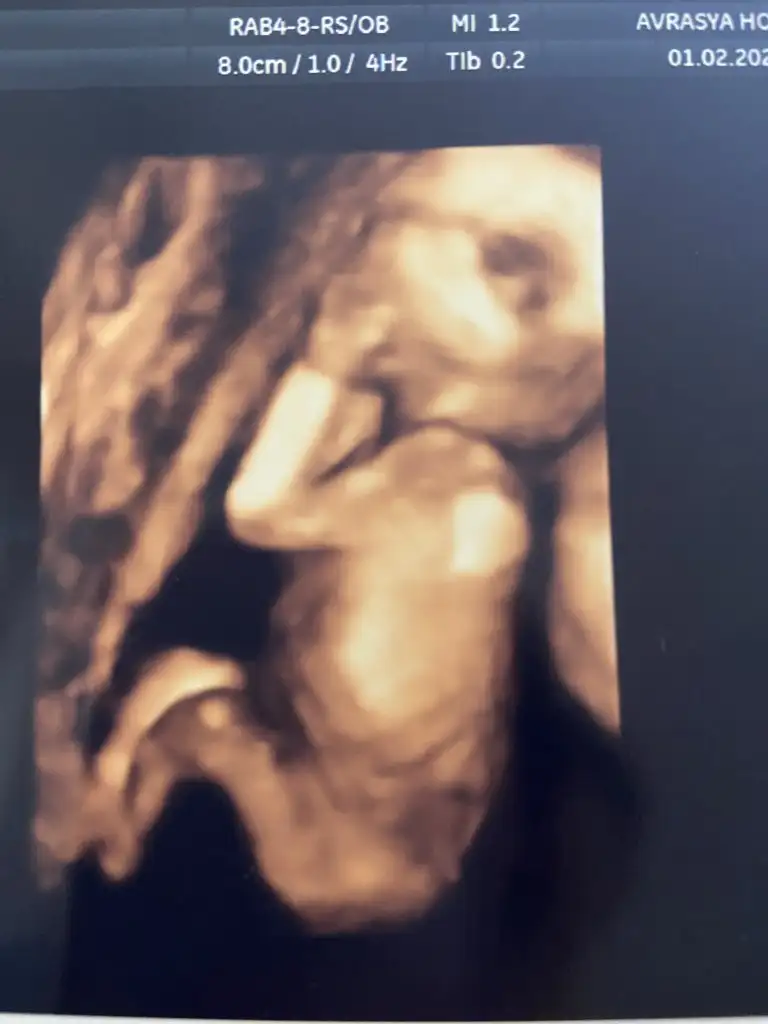

Senin değişse benimde umudum olacaktı ama 2.ciye artıkEvet hanımlae gittimmmmm ve bebişimi gördüm içim rahatladı 200gr boyuda 17 cm çıktıveee cinsiyetim değişmedi kesin erkek artık alışverş yapabilirsin dedi , yami değişmedi cinsiyet ama herşey güzel dedi rahatladım